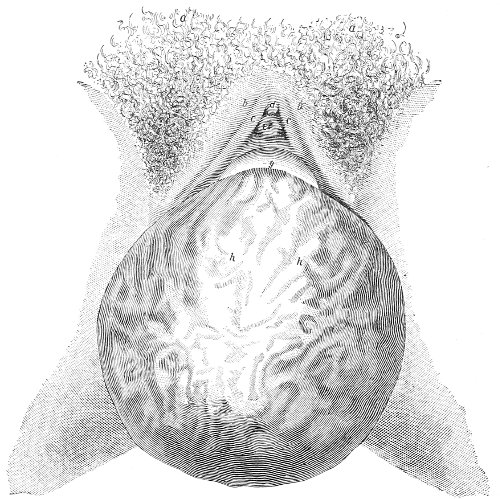

Vaginal and Bimanual Examination.—Having examined and noted the condition of the external genitals, the physician should next proceed to examine the vagina. The index finger of the right or the left hand should be gently introduced into the vagina. The condition of the vaginal walls, and the direction, consistency, form, etc. of the vaginal cervix, may be determined. The shape and size of the os uteri should be noted. The ulnar edge and the tips of the fingers of the other hand should then be placed upon the abdomen, immediately above the symphysis pubis, and gently pressed backward and downward toward the vaginal finger 24 (Fig. 2). In this way the various pelvic organs, the uterus, Fallopian tubes, ovaries, and ureters, may be palpated between the two hands, and their position, size, shape, and consistency may be determined. Such an examination is, of course, made much more easily in a thin woman than in a fat one. A thin woman a few weeks after labor may be examined most easily, on account of the relaxation of the abdominal and vaginal walls.

Fig. 2.—Bimanual examination.

This is called the bimanual method of examination, and the student will find that as he acquires practice in this method he will gradually depend less upon examination by the uterine sound and the speculum, and will rely altogether upon his sense of touch, his ability to palpate.

It matters not which hand be used in making the vaginal examination. It will, however, be found that the hand that is used the more frequently will become the more proficient.

In making the bimanual examination the structures 25 should be palpated methodically in order. The vaginal finger notes the condition of the cervix uteri. If the fundus be in the normal position, the uterus can then be taken between the abdominal hand (upon the fundus) and the vaginal finger (upon the cervix) (Fig. 3). The shape, size, mobility, and consistency are noted. The vaginal finger is then passed anteriorly and laterally toward either uterine cornu, while the abdominal fingers pass over to the posterior aspect of the same cornu. The ovarian ligament and the proximal end of the Fallopian tube may thus be felt. Passing farther outward, the whole of the tube and the ovary may be examined. The same procedure is then applied to the opposite side.

Fig. 3.—Bimanual examination; median sagittal section of the pelvis.

The condition of the ureters may be determined by placing the vaginal finger in either lateral vaginal fornix and drawing it outward and forward, when these structures will pass over the end of the finger. When the 26 ureters are indurated by inflammation they can be plainly felt.